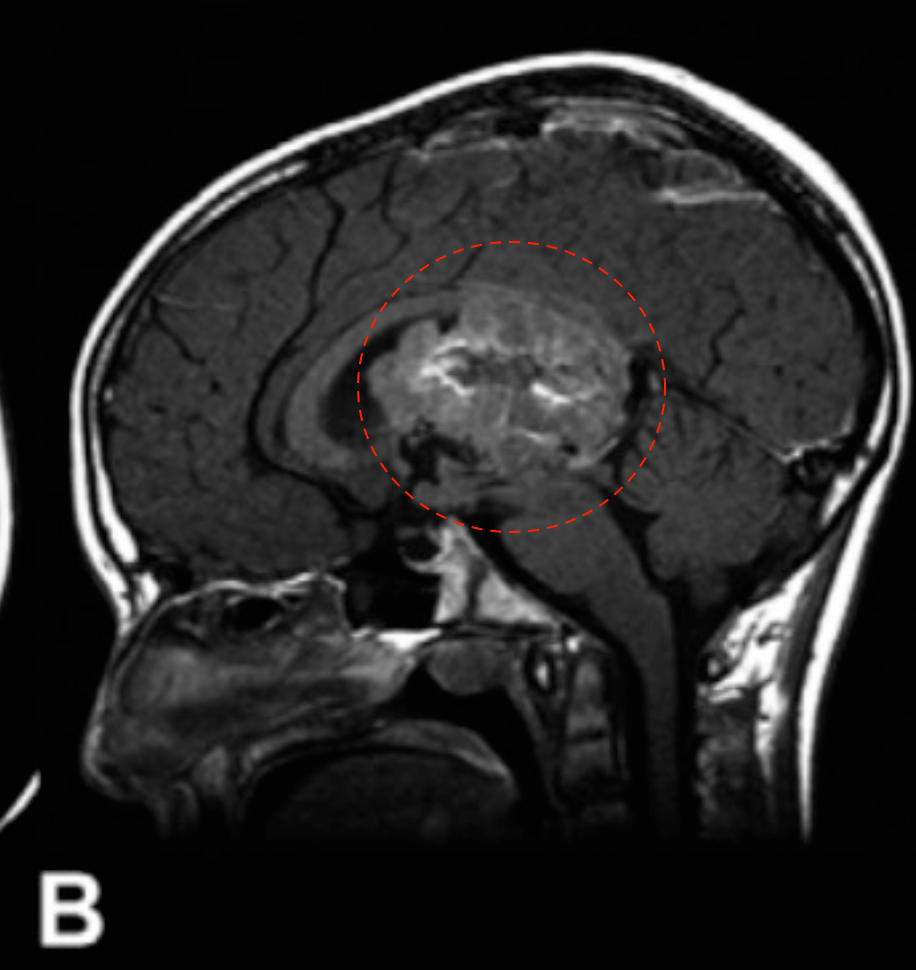

12岁男孩,因出现近3周的头痛和急性恶化而入院治疗。

(B & C)磁共振成像显示一个可能起源于透明隔的异质性强化肿瘤,填充在侧脑室和第三脑室的大部分区域。